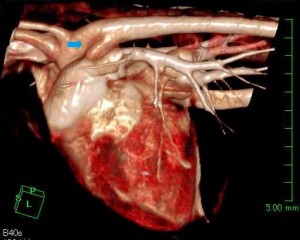

外科治療では開胸手術により動脈管を糸で結紮し血流を遮断します。当院では外科手術をよりスムーズに行う目的で術前のCT撮影で動脈管を確認することおこなっています。

また術前のCT検査にて動脈管の確認を行い、術後のCT検査にてその部分の血流が遮断されていることを確認した。

オペ前CT(矢印が動脈管)

オペ後